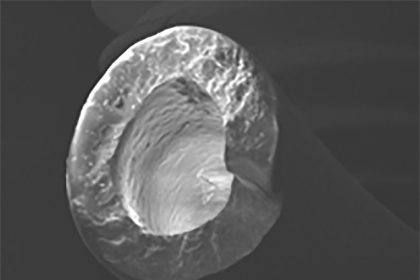

The port catheter, first approved for use by the FDA in 1981, is a system consisting of two primary components: an injection port and a polyurethane or silicone catheter. The injection port has a raised center, or “septum,” where the needle is inserted for delivery of the medication or blood transfusion. The medication or blood is carried from the port into the bloodstream through a small, flexible tube, called a catheter, that is inserted into a blood vessel.

According to manufacturers’ marketing materials, the polyurethane catheter “has less propensity for surface biodegradation, making it more resistant to environmental stress cracking.” The polyurethane or silicone comprising the catheter in the port-a-cath is comprised of a polymeric mixture of the thermoplastic and barium sulfate, a soft metal compound which is visible in certain radiologic studies (most commonly a lineogram).

Barium sulfate is known to contribute to reduction of the mechanical integrity of polyurethane/silicone en vivo as the particles of barium sulfate dissociate from the surface of the catheter over time, leaving microfractures and other alterations of the polymeric structure and degrading the mechanical properties of the catheter.

The mechanical integrity of a barium sulfate-impregnated polyurethane is affected by the concentration of barium sulfate as well as the homogeneity of the modified polymer. The manufacturing process in constructing in a significant portion of the implanted catheters involve too high a concentration of barium sulfate particles, leading to improperly high viscosity of the raw polyurethane or silicone before polymerization and causing improper mixing of barium sulfate particles within the polymer matrix.

This improper mixing of the barium sulfate and polymer, as noted in numerous studies over the past forty years, can lead to pockets of barium sulfate and entrapped air being distributed through the catheter body and on the inner and outer surfaces of the catheter tube. This defect in the manufacturing process led to a heterogeneous modified polymer which led to an irregular catheter surface replete with fissures, pits and cracks. In addition to the degradation of the structural integrity which can lead to the catheter tube breaking apart and fragments passing through the blood stream into the heart or lungs, the roughened catheter surface also leads to the collection and proliferation of biofilm and fibrinous blood products, thereby drastically increasing the risk of infection and thromboembolism.